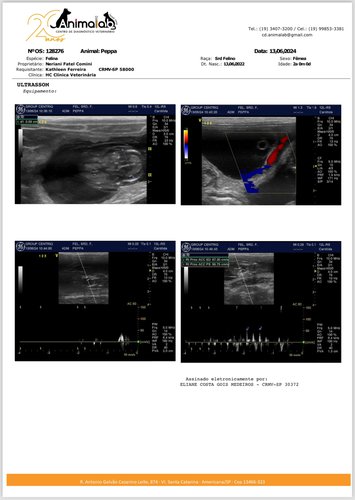

Laudo gestacional + cirurgia (cesária/castração):

No laudo foram visualizados 3, mas eram 6 fetos, todos já sem vida. Ela ter resistido super bem já é um milagre! Vitória na guerra, queridos.